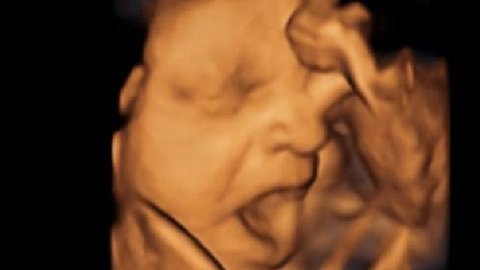

17. 아기는 엄마 뱃속에 있을 때 하품을 함

http://www.bbc.co.uk/news/uk-england-cumbria-20445286

하품한다고 함...